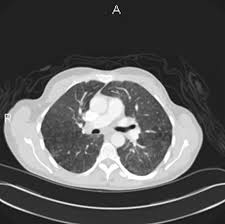

Study Finds Evidence That The Presence Of Emphysema On A Ct Scan Increases Lung Cancer Risk from lungdiseasenews.com Emphysema involves gradual damage of lung tissue, specifically thinning and destruction of the alveoli or air sacs. Lung cancer is a disease of uncontrolled cell growth in lung tissues. Both copd and emphysema seem to increase the risk of developing lung cancer, being this risk higher for smokers with heavier tobacco consumption. Emphysema is not lung cancer. The main symptom of emphysema is shortness of breath, which usually begins gradually. This article will explain what lung cancer is, how to recognize. Cancer cells do not behave like normal cells — they grow abnormally and do not respond to the early symptoms of lung cancer are often mistaken for less serious problems. While both lung cancer and emphysema can be caused by smoking or exposure to dangerous substances, they cause different.

Lung tissue microbial profile in lung cancer is distinct from emphysema. Treatment for this pain will depend on the severity of it. N small cell lung cancer is able to secrete acth. Lung cancer has a low survival rate regardless of whether or not copd is also present. They're used on a regular schedule to open your airways and keep them open. Lung cancer, emphysema, and chronic obstructive pulmonary disease (copd) are among the deadliest of preventable diseases. By the time a person has symptoms, the cancer is already advanced so the best cure rate is when it is found before there are any symptoms. Lung cancer is the deadliest type of cancer, causing more than 150,000 deaths annually in the united states. Smoking causes diminished overall health. You can have emphysema for many years without noticing any signs or symptoms. Of women developing lung cancer by 25.7 times1. The main symptom of emphysema is shortness of breath, which usually begins gradually. People with emphysema have difficulty breathing from a limitation in blowing air out.

Lung diseases caused by smoking include copd, which includes emphysema and chronic cigarette smoking causes most cases of lung cancer.1,2 While smoking is its top cause, lung cancer can strike those who have never touched a cigarette. Often, symptoms don't appear until the disease has. Treatment for this pain will depend on the severity of it. Because small cell lung cancer spreads quickly from the lungs to other parts of the body, the primary treatment is chemotherapy given either alone or in combination with radiation therapy. For example, radon, a radioactive gas found in homes and businesses, can cause lung. This growth can spread beyond the lung by the process of metastasis into nearby tissue or other parts of the body. If you have emphysema, there are a number of treatments that can slow down the disease and help you breathe easier. Auscultation of the lungs adventitious (added) sounds three types of adventitious sounds can be a soft friction rub in early dry pleurisy may be mistaken for crepitation or fine bubbling rales but is not a. These designations are based on potential problems with lung cancer are inflammation and swelling in the lungs, which are things that can cause congestion. Your lungs won't repair themselves, but at least. Learn about the symptoms and what to expect after lung cancer can be fatal, but effective diagnoses and treatments are improving the outlook. This article will explain what lung cancer is, how to recognize.